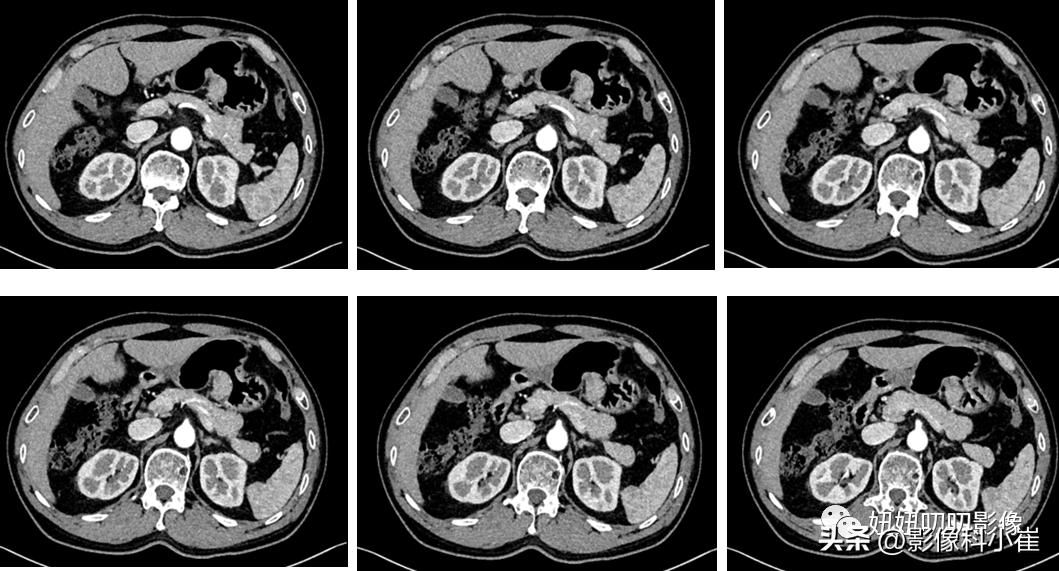

胃体小弯侧胃壁粘膜下见不规则软组织密度灶,局部与胃壁界限欠清,最大截面约 2.9×1.9cm,增强扫描呈明显不均质强化,周围脂防间隙尚清晰,未见明显异常肿大淋巴结。

①:病理是异位胰腺;

②:CT上异位胰腺多位于胃窦部,向腔内生长、边界不清,部分病灶内可见“导管征”,增强呈中度均匀强化;MRI上异位胰腺的信号与正常胰腺相似,可表现为胃、十二指肠或小肠壁内富血供的软组织肿块,少部分患者表现为胃肠道管壁的环形增厚。